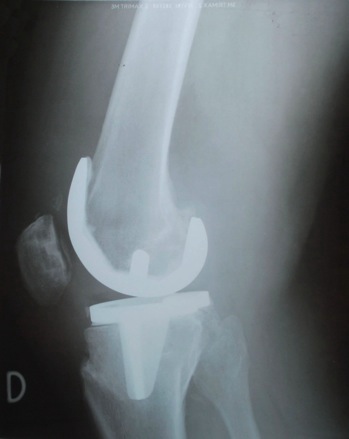

Analyse de radiographies

Analyse différentes radiographies. Essaye de reconnaître:

les différentes parties représentées: os, articulations,...

les malformations, les déplacements, les fractures.

l’âge des sujets: zones de croissances.